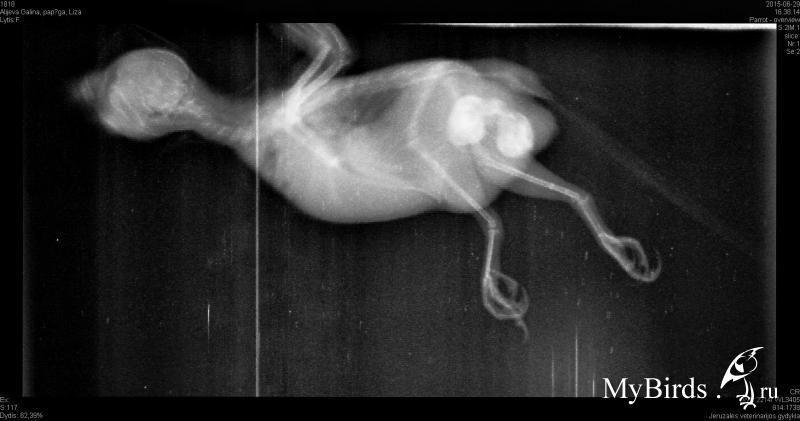

galiuniaaa Опубликовано 29 июня, 2015 Автор #12 Опубликовано 29 июня, 2015 (изменено) Снимкиврча адекватный попался. сказал такого не видел и не может понять что за соединение между ними. Это яйца?? Изменено 29 июня, 2015 пользователем galiuniaaa

Zosia Опубликовано 29 июня, 2015 #14 Опубликовано 29 июня, 2015 galiuniaaa, постучите в личку Зосе. На моей памяти- ВТОРОЙ случай ЖИВОЙ двухяйцевой самки... все написала в личке.

galiuniaaa Опубликовано 29 июня, 2015 Автор #15 Опубликовано 29 июня, 2015 На моей памяти- ВТОРОЙ случай ЖИВОЙ двухяйцевой самки... все написала в личке. Спасибо большое !!Теперь нам нужен пряморукий врач...

Delfin Опубликовано 29 июня, 2015 #16 Опубликовано 29 июня, 2015 (изменено) а вы еще рентген не хотели делать! Я в ШОКЕ сижу...не думала что ТАКОЕ бывает... ожидала всего что угодно, но ТАКОГО... Галина, вечно у вас как то все... странно.Но ЖЕЛАЮ ВСЕГО НАИЛУЧШЕГО!!!держитесь! и хорошего вам ВРАЧА! Изменено 29 июня, 2015 пользователем Delfin

galiuniaaa Опубликовано 29 июня, 2015 Автор #17 Опубликовано 29 июня, 2015 а вы еще рентген не хотели делать! Я в ШОКЕ сижу...не думала что ТАКОЕ бывает... ожидала всего что угодно, но ТАКОГО... Галина, вечно у вас как то все... странно.Но ЖЕЛАЮ ВСЕГО НАИЛУЧШЕГО!!!держитесь! и хорошего вам ВРАЧА! Не говори...Я сама сижу в шоке..Я ожидала чего угодно но чтоб 2 !!! Надеюсь после долгих мазаний и паровой ванны она разродится сегодня, хоть одно чтоб вышло...Ждем до утра и сразу в вет. могли сегодна пробовать но я хотела услышать Зоси вердикт... Вет.врач сказал яйца и неординарный случай но он в сомнениях был насчет этого соединения,как такое может быть.Он фото отправил коллегам, но мы завтра летим в клинику и по инструкции Зоси будем все пытаться достать.... Пожелайте нам удачи, сейчас нам она нужна благо птица держится и ведет себя как обычно ,после сильнейшего стресса перенесенного в клинике..

Zosia Опубликовано 30 июня, 2015 #38 Опубликовано 30 июня, 2015 У меня сомнения в том что нет скорлупы, как такое может быть и что делать? ( Надеюсь Зося скажет как такое может быть...Жидкость идет а скорлупки нет Я подозреваю,что ОБА яйца были с мягкой (малокальцинированной) скорлупой. Только так я могу объяснить появление двух яичек сразу в яйцеводе. Т.е появилось первое, из-за мягкости нет достаточного давления на сленки яйцевода,соответственно- нет нужного сигнала на ПСН, и нет достаточной "родовой деятельнсоти". Через 36 часов выходит следующее яичко,продвигается дальше,упирается в первое- и получаете вашу ситуацию. Из-за мускульных сокращений ("схваток") яйца раздавливаются, давление опять падает,родовая деятельность прекращается.Как-то так мне видится механика вашего случая...